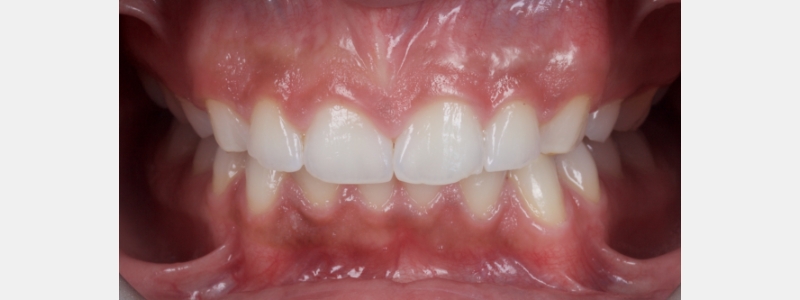

A diagnosis of altered passive eruption (APE) alongside tooth surface loss (TSL) secondary to parafunction was made for a referred female patient in her early 20s who complained of having“short, fat, baby teeth.” Due to her age, she was treated with a simple gingivectomy (after bone sounding), nightguard vital bleaching (NGVB), and additive edge bonding.

The worn incisal edges were restored with edge bonding, a new technique for restoring worn dentition. This should be regarded as a multiple Class IV restoration.